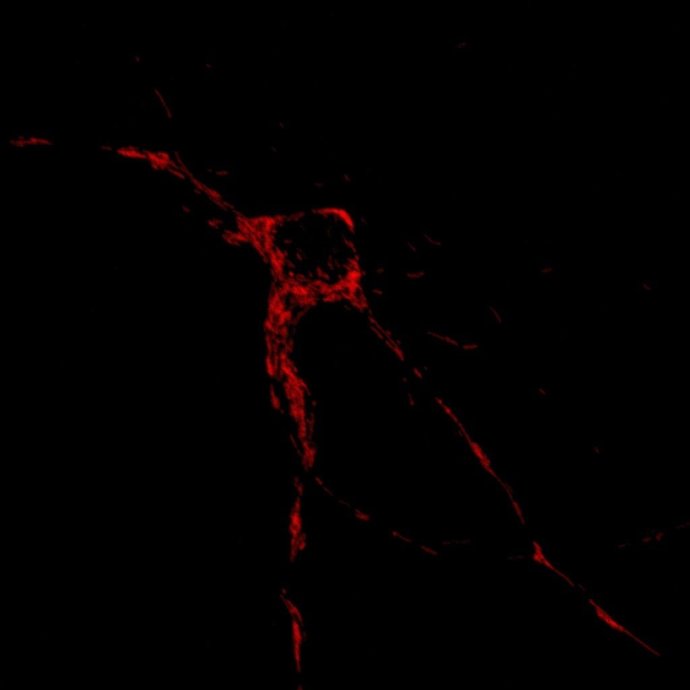

En Rojo, Localización De Mitocondrias En Una Neurona

Científicos del Instituto de Investigación Biomédica (IRB) de Barcelona han logrado identificar un grupo de seis genes cuya función es regular el movimiento y posición de las mitocondrias en las neuronas, un papel clave en el funcionamiento y viabilidad del cerebro.